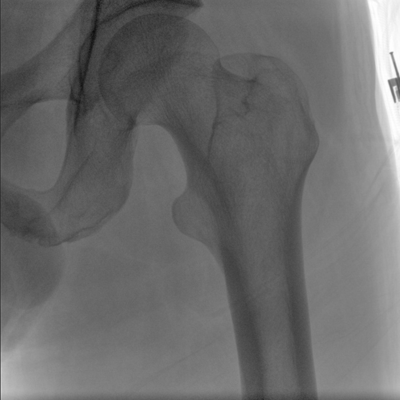

臨床適用科室:骨科、普通外科、矯形外科、創(chuàng)傷外科、泌尿外科、脊柱外科、疼痛外科、消化科、婦科等科室。

大尺寸動(dòng)態(tài)平板探測(cè)器,高DQE、低噪聲、圖像清晰。采用多分辨率圖像增強(qiáng)處理技術(shù),不同部位不同圖像處理算法,滿足客戶多樣化的需求。